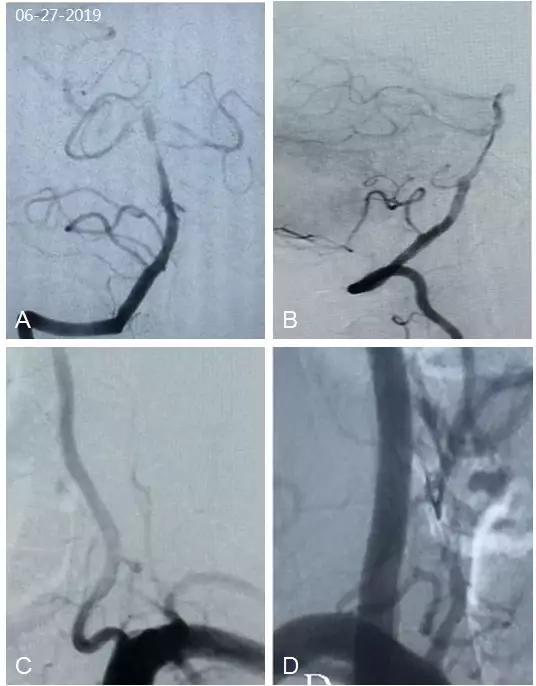

全脑血管造影(2019-06-27):基底动脉中远段重度狭窄,左椎动脉V1段迂曲(图3);左颈内动脉经后交通动脉向基底动脉中远段代偿供血(图4)。

图3

图4